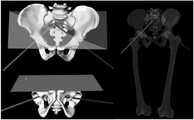

도 14의 좌측은 심각한 골반 불연속성을 갖는 환자의 3차원적 모델 표상이다. 우측에는 좌측에 나타낸 상기 환자의 골반의 3차원적 모델에 대한 일 예가 도시된다.

The left side of FIG. 14 is a three-dimensional model representation of a patient with severe pelvic discontinuity. On the right, an example of a three-dimensional model of the patient's pelvis shown on the left is shown.